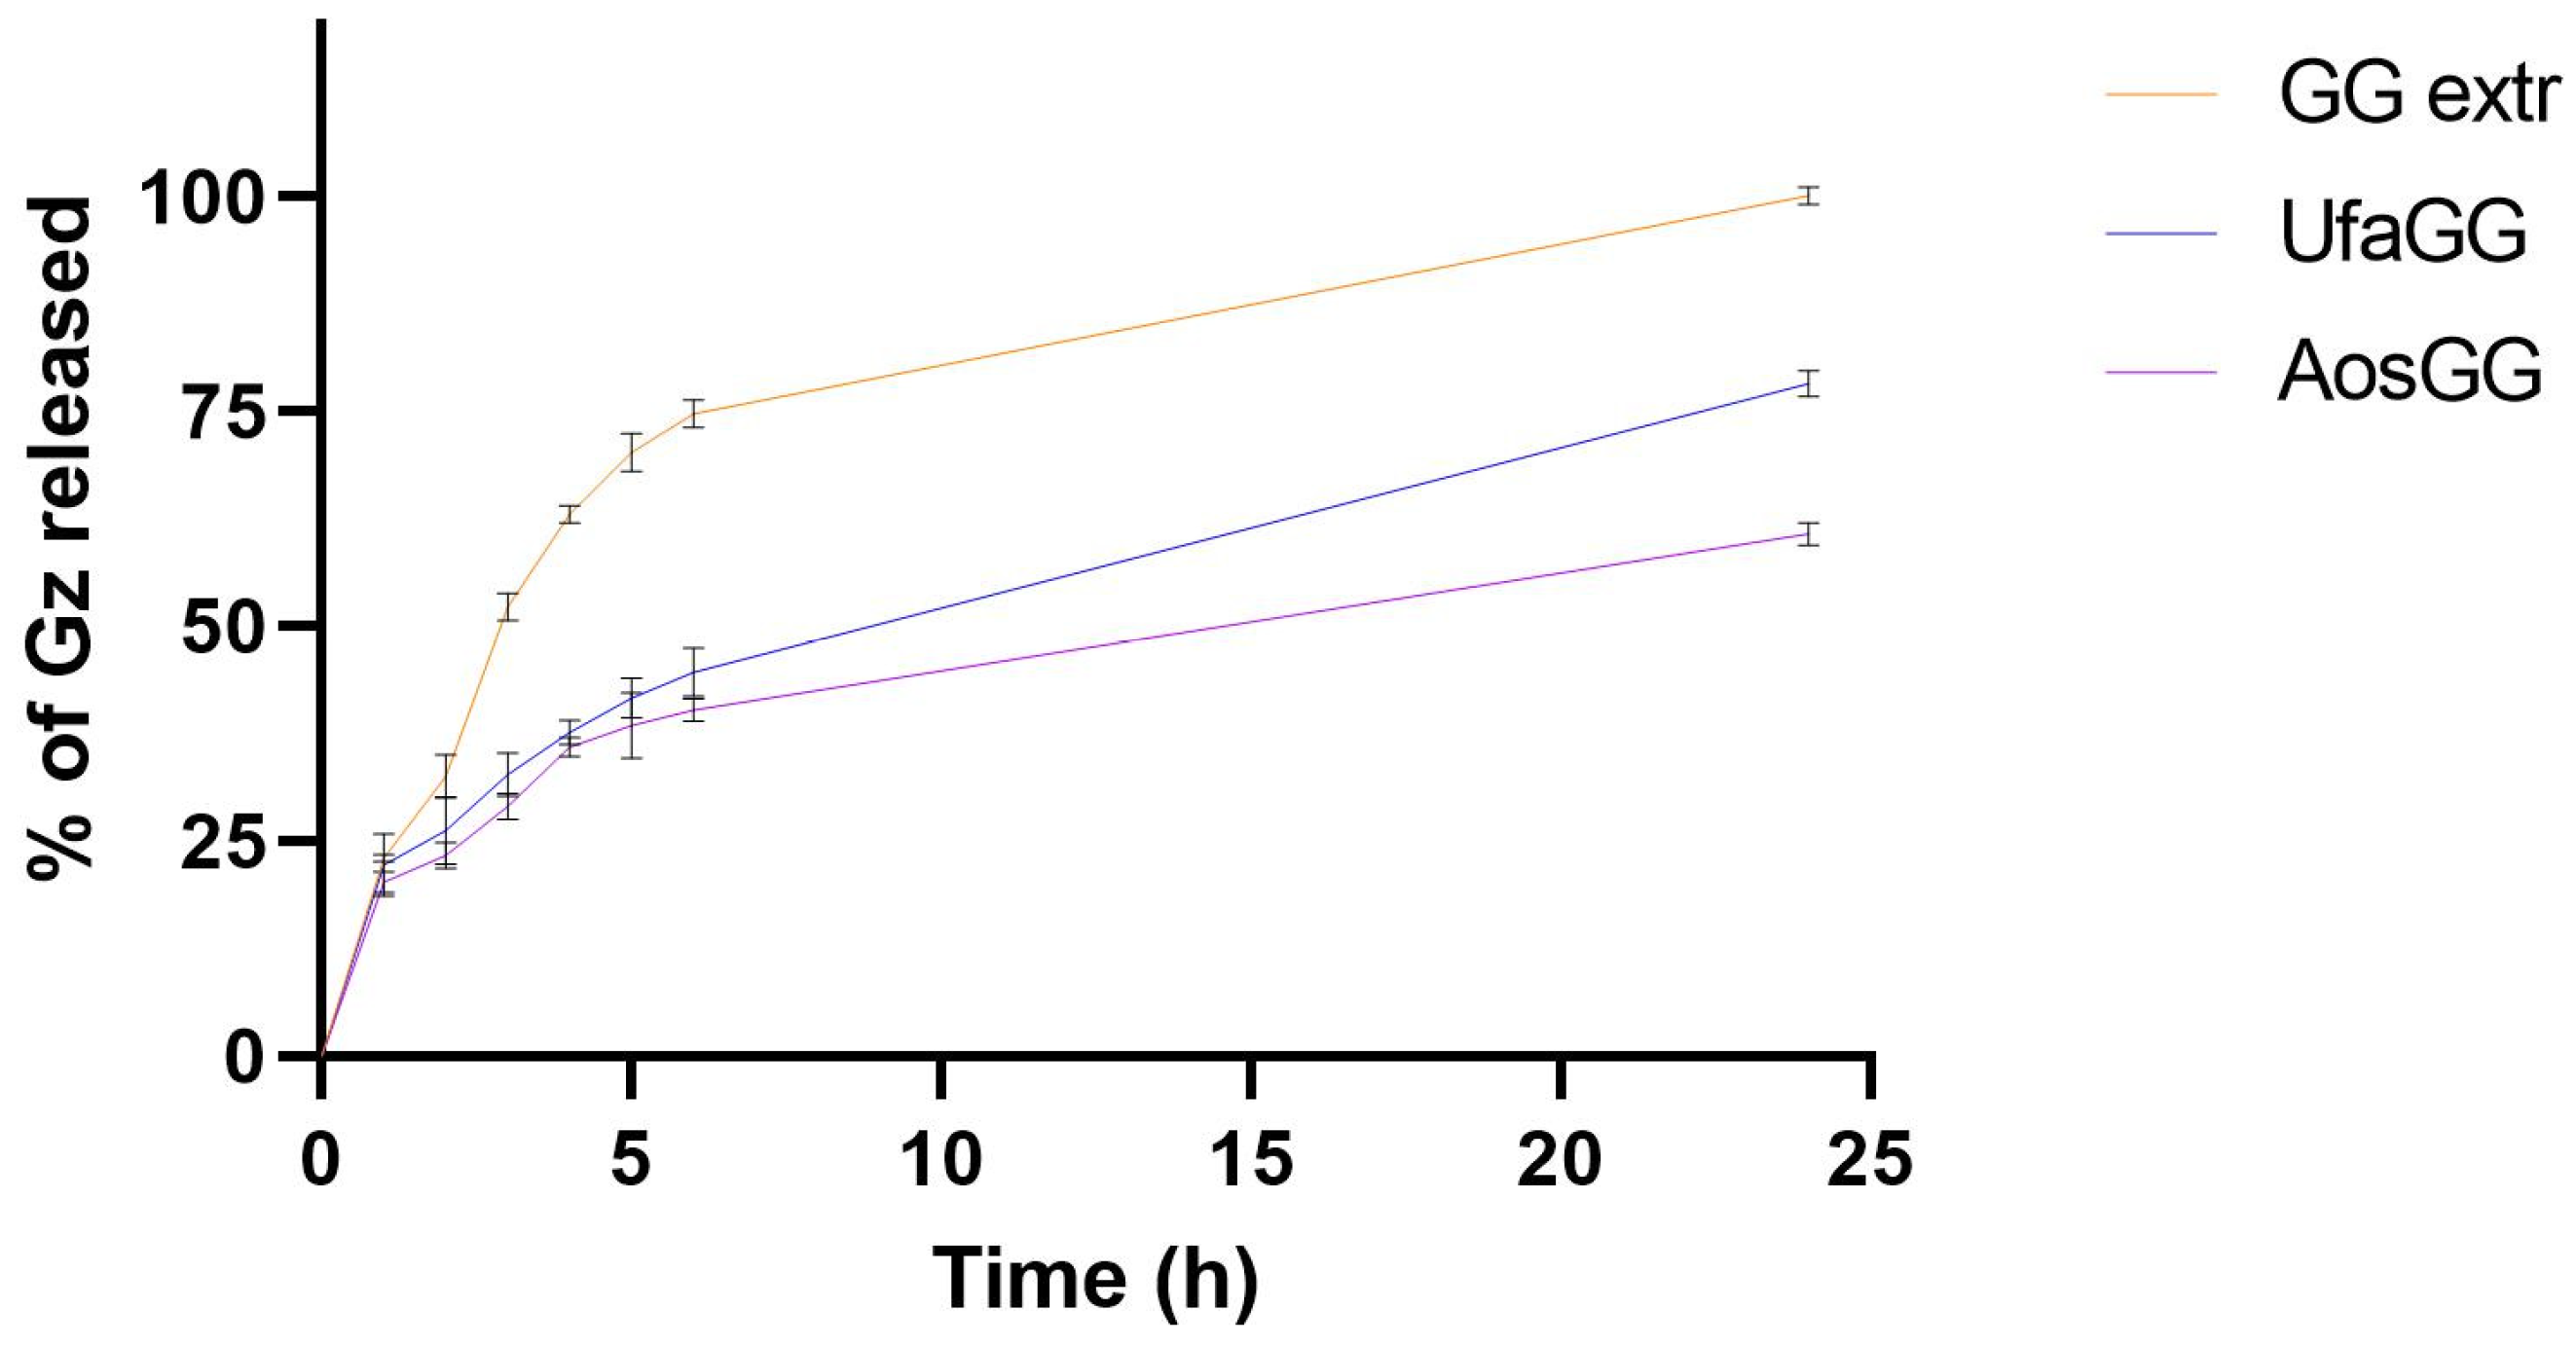

2.5. In Vitro Release Studies

3.6.4. In Vitro Release Studies